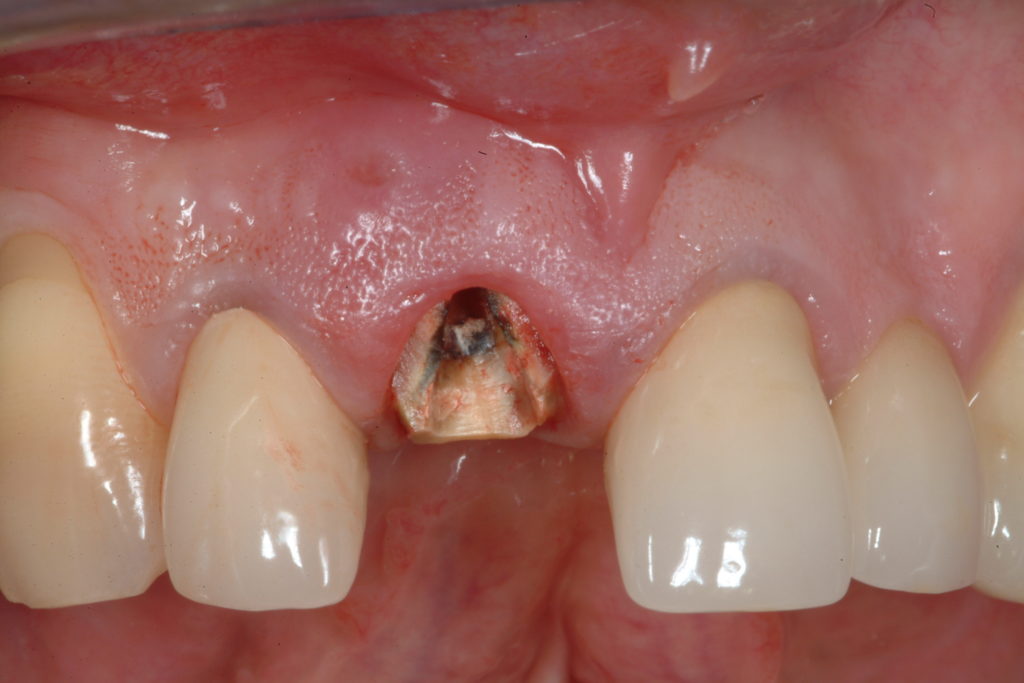

Clinical case

Immediate post-extraction implant

In many cases, when an irrecoverable tooth is extracted, an implant can be immediately inserted, in the same session, without having to wait for the gum to heal and, therefore, avoiding additional surgery and anesthetic at a later date. This procedure is called Immediate post-extraction implant.

In various cases of post-extraction implants, immediate loading can also be carried out, when there are important aesthetic requirements, for example an incisor. the specialist will safely evaluate this possibility.

After the right amount of healing and stabilization time, the temporary crown is replaced with a more precise abutment and dental crown built by our laboratory, specialized in implant-prosthetics. These are customized and made in a way to be indistinguishable from the other natural teeth. The result is that the tooth has been replaced naturally, without damaging the neighbouring teeth and preventing bone resorption.